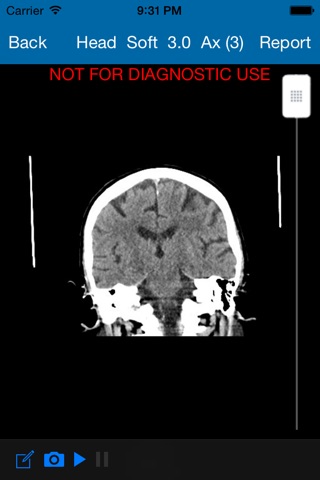

PHMI Mobile is an app for viewing x-ray studies performed at Peninsula Health. Peninsula Health is a leading provider of radiology services in the Frankston and Mornington Peninsula areas. Access to PHMI Mobile is for registered referrers only. Please contact Peninsula Health Medical Imaging Department if you are a referrer and wish to have access to radiology reports and images via PHMI Mobile.